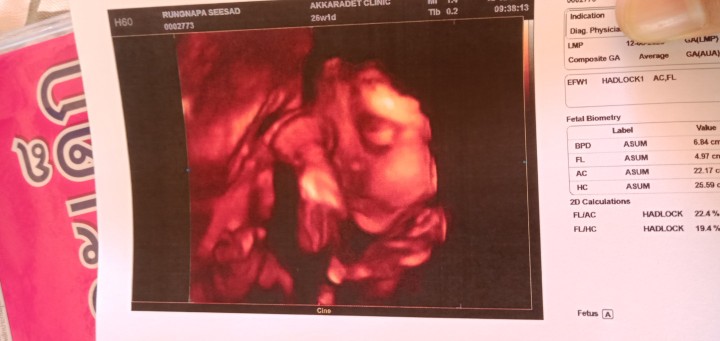

รูปตอน26วีค ตอนนี้35วีคแล้วจ้า